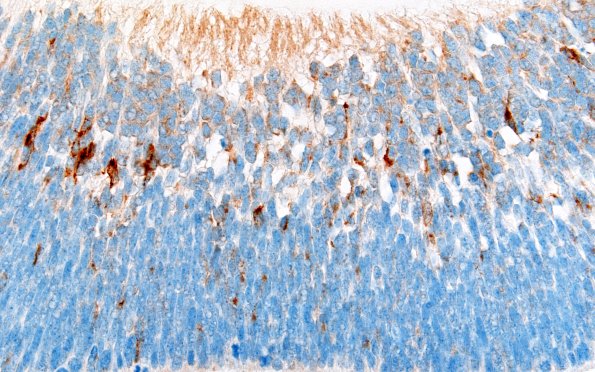

Synaptophysin stains the terminal aspects of presumed rods and cones (arrowhead, 1K2).